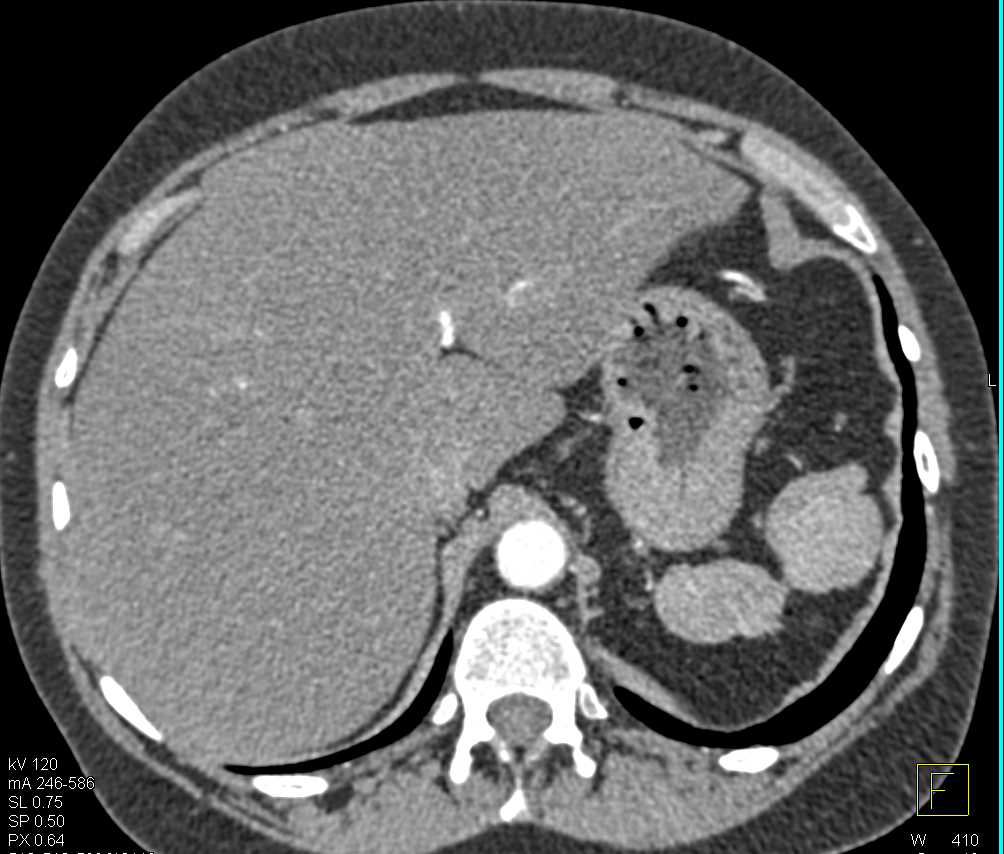

Complex Liver Cysts with Thickened Wall